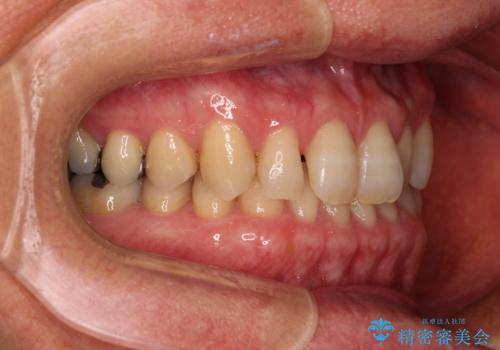

- 前歯のデコボコと隙間の空いた歯列を気にして来院された患者様です。

下顎前歯が隠れるほどのディープバイトにより、強い咬合力と突き上げで上顎歯列に隙間が空いている状態でした。

手前に傾斜している奥歯をワイヤー装置で立ち上がらせ、咬み合わせの高さを挙上することで突き上げを解消し、空隙歯列を改善していくこととしました。